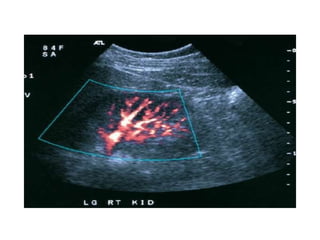

The kidneys can be injured by blunt or penetrating trauma, requiring timely medical evaluation. The kidneys are normally protected by back muscles but can be damaged by severe impacts or objects piercing the skin. Blunt trauma may cause bruising while penetrating injuries like gunshots can enter elsewhere and travel to the kidneys. Most kidney injuries are minor but evaluation with imaging tests like ultrasound or CT scans helps classify the injury and guide management, which may include rest, antibiotics, surgery, or nephrectomy in more severe cases.